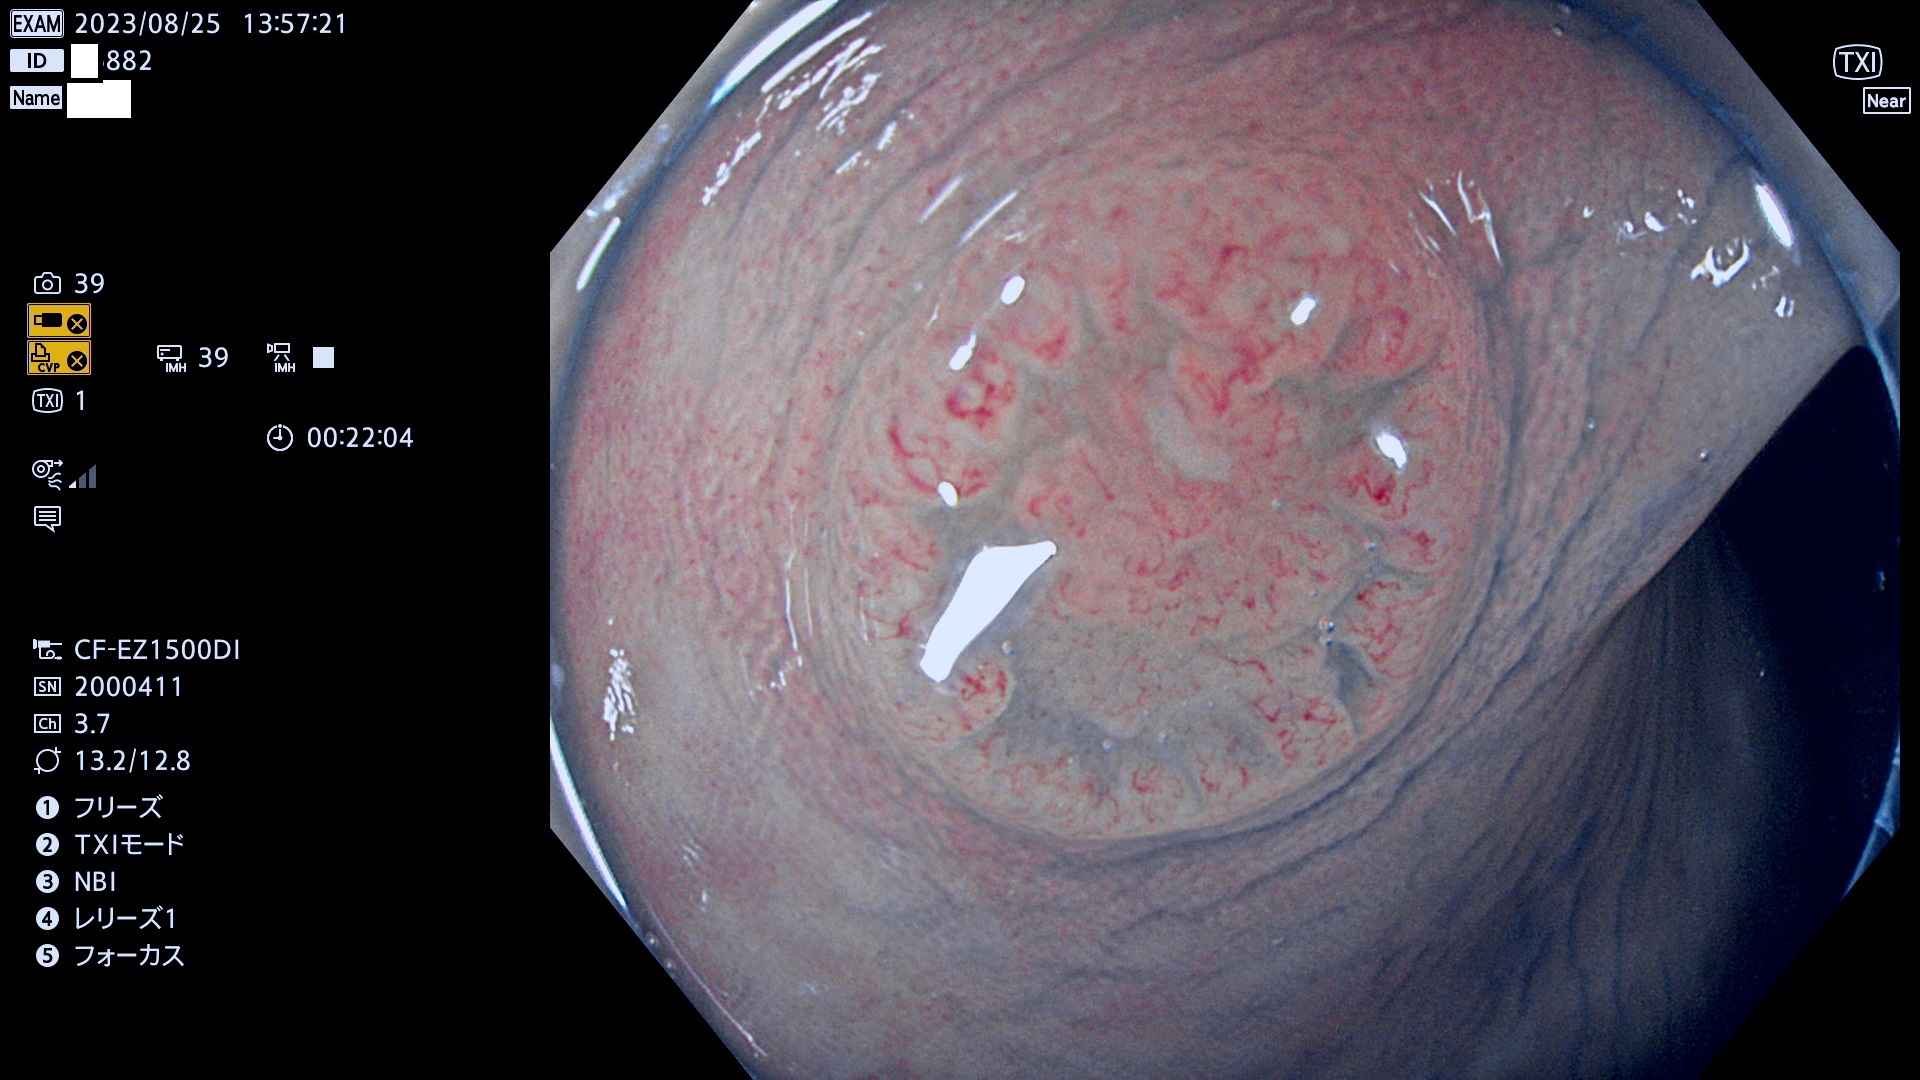

表面型腺腫(Flat Adenoma)の中で、完全に平坦な物をUb、陥凹している物をUcと呼びます。平坦隆起型(Ua)よりも、発見が難しく危険な病変です。このタイプは「内視鏡後・大腸癌の重要犯人」であり、この発見率は「腺腫発見率」よりも、重要な意味があります。

毎週の検査(木・金・土・日)に発見されたUb、Uc型・腺腫を、その週の日曜の夜にUPし1週間、提示します。

抽出の対象期間 2023年8月24日(木)〜8月27(日)の4日間(48件の検査)9件